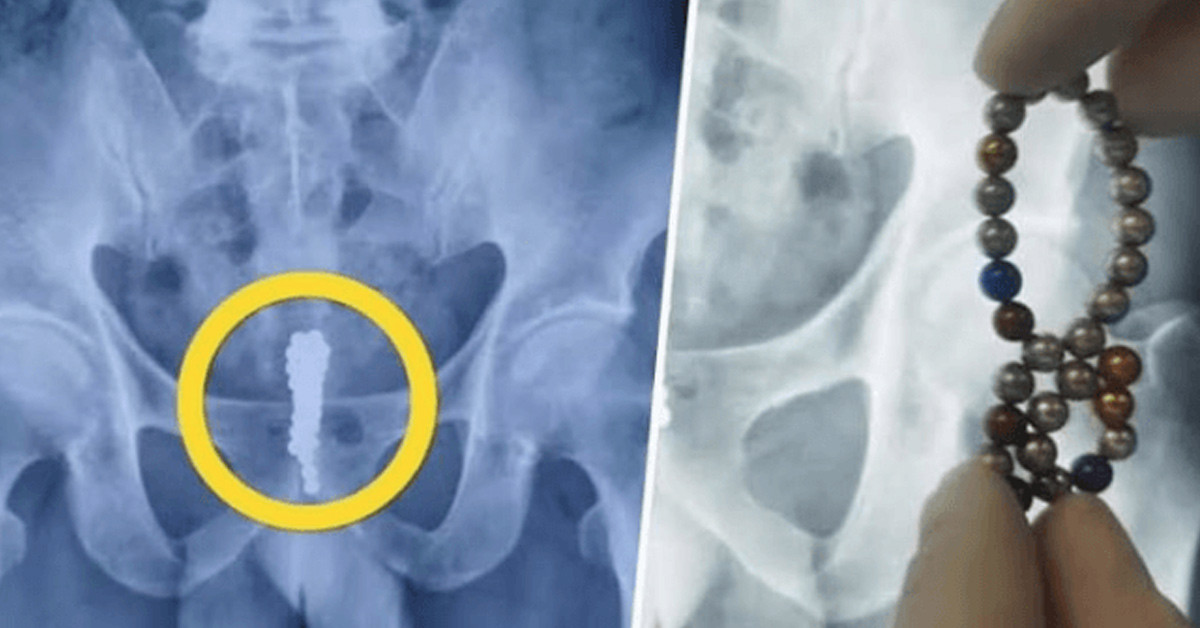

Röntgen çekilen Hua'nın içinde yer alan 53 topun iki sütuna hizalanan posterior üretra bölgesinde sıkışıp kaldığı ortaya çıktı. Ameliyat alınan Hua'nın erkeklik organından 53 tane top çıkarıldı ve 14 yaşındaki çocuk eski sağlığına kavuştu. 14 yaşındaki Jiang Hua'nın erkeklik organına 53 tane manyetik top sokması Çin medyasında da büyük ses getirdi.